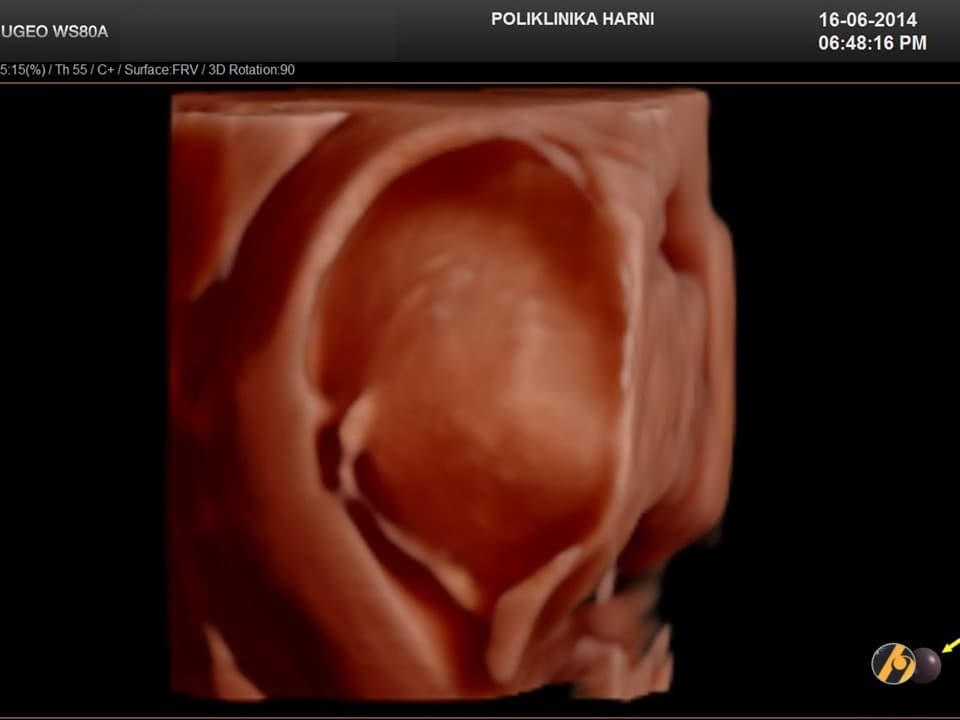

Dijagnoza

Dijagnoza mioma postavlja se temeljem anamnestičkih podataka, ginekološkog i ultrazvučnog pregleda. Ponekada su, osobito kod gigantskih mioma nužne dopunske metode kao što su intravenska urografija, CT ili MRI zdjelice, kako bi se u planiranju operativnog zahvata mogao procijeniti utjecaj mioma na okolne organe, a time i rizik povrede tih organa tijekom operacije.

Dijagnoza se postavlja ginekološkim pregledom i slikovnim pretragama.